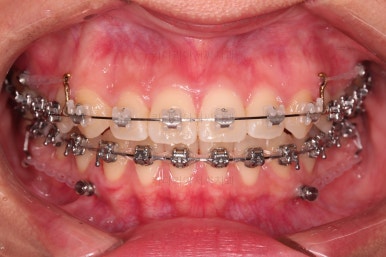

초진 시 입안의 모습입니다.

치열이 많이 삐뚠 것은 아니지만 앞니쪽이 삐뚤어 있고요. 아랫니 사이사이에 고루 틈새가 있네요.

윗니는 삐뚤고(공간부족), 아랫니는 틈새가 있다면(공간 과잉) 그 부조화는 부정교합을 의미합니다.

어금니 교합이 전반적으로 아랫니가 뒤로 빠져있는 교합이어서 맞물림이 좋지 못한 상태였어요.